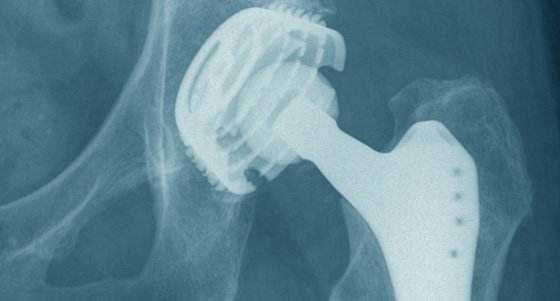

髋关节置换术(THA)是一种重建髋关节功能的骨科手术。可彻底治疗髋关节病变,恢复关节解剖结构,消除疼痛,恢复患者行走功能。但除了手术成功之外,髋关节功能的实现还需要髋部周围肌肉、韧带、神经的支撑,以及全身状况的保障。

* 检查X线片,了解手术关节是否有畸形、增生、排列等影像学变化,作为手术的重要参考。